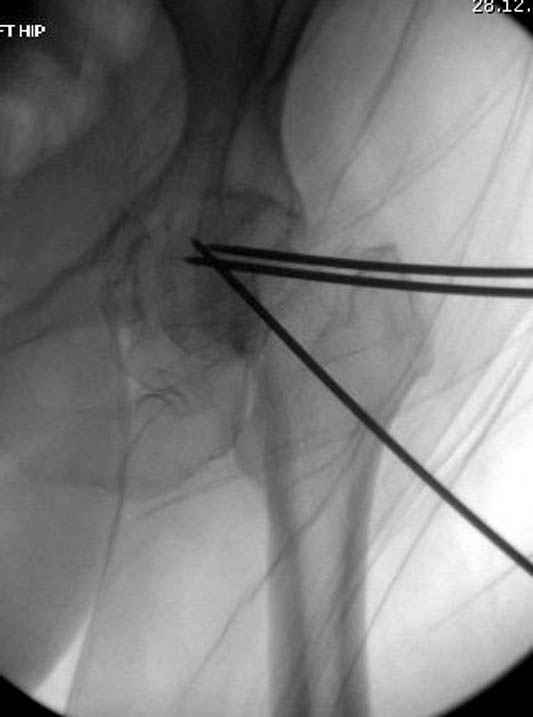

В данный момент скелетное вытяжение поучается через перелом шейки, а фиксированный перелом шейки будет участвовать в процессе вытяжения через каннюлированные шурупы.

Перелом шейки смогли зафиксировать через пару дней, ацетабулум до сих пор не оперирован, на вытяжении.